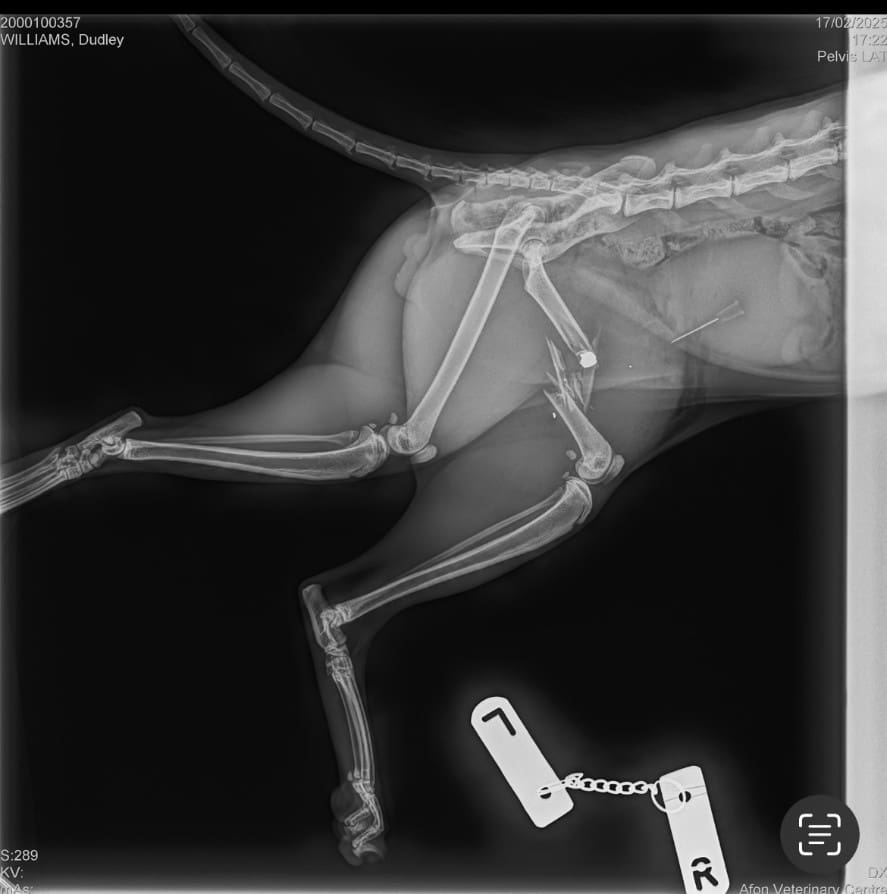

He was spotted by a neighbour limping home who alerted his owners – Ceris Williams and Tom Tyson – and they took him to the vets where it was discovered the pellet which had shattered his hip and was stuck in between the muscle of his back left leg. As a result he had to have his back left leg amputated.

She said at the vets they thought he could have suffered a sprain as he was limping but after three X-Rays they discovered he had been shot and subsequently had to have an amputation.